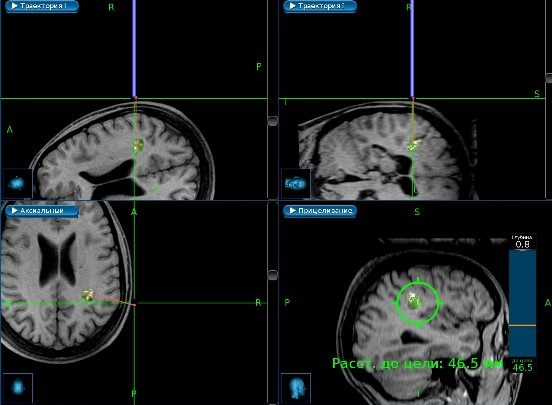

- 7. Краткое описание хода операции. После фиксации головы в скобе Мейфилда осуществлена разметка доступа с использованием навигационной станции Medtronic Stealth Station S7. В правой теменно-височной области выполнена костно-пластическая трепанация черепа. Далее под интраоперационной навигацией, cопряженной с микроскопом Pentero OPMI 900, определена наиболее безопасная траектория доступа через борозду между угловой и постцентральной извилинами. При этапном прямом монополярном стимулировании коры подтверждено отсутствие двигательных центров в проекции доступа.

Скриншот системы интраоперационной навигации с планированием доступа к мальформации.